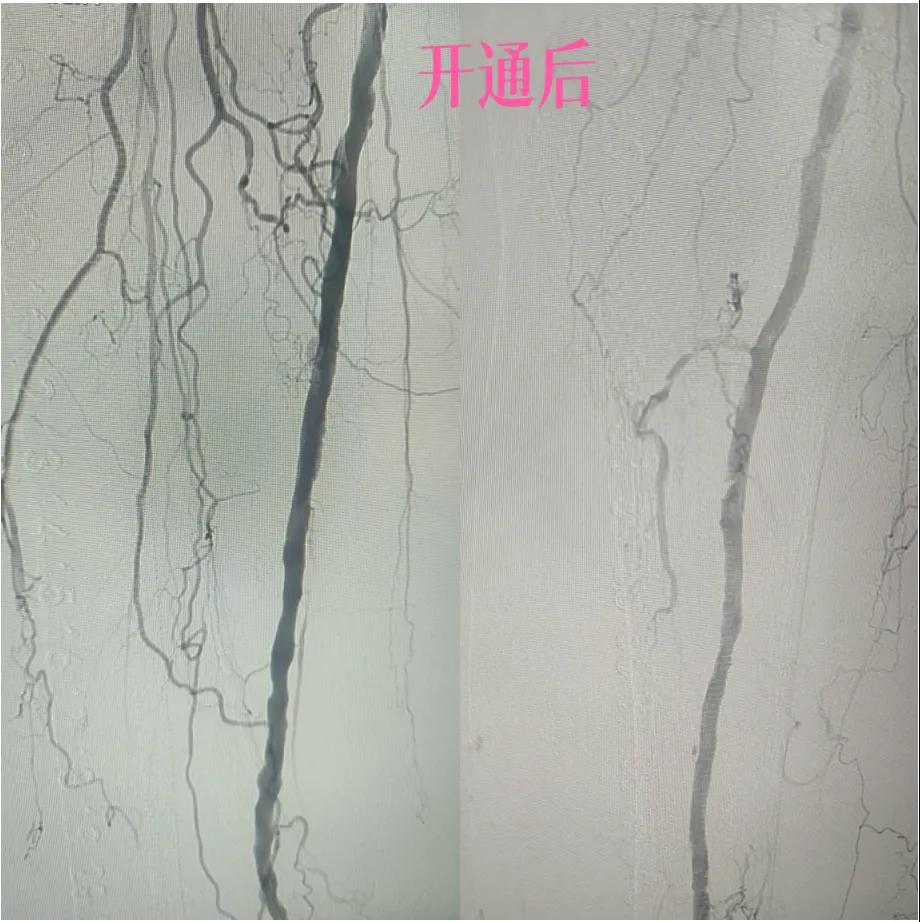

漯河市中醫(yī)院:微創(chuàng)介入:球囊擴(kuò)張術(shù),“撐”開(kāi)生命通道

近日,漯河市中醫(yī)院外二科血管外科介入團(tuán)隊(duì)利用微創(chuàng)介入技術(shù)成功保住一患者患肢。

據(jù)悉,患者以“右足足趾疼痛伴第三足趾壞疽4月余”為主訴來(lái)院就診,查體患者右足第三趾末端呈壞疽狀,已結(jié)痂,足趾根部及足背部紅胖、壓痛,右側(cè)足背動(dòng)脈,脛后動(dòng)脈搏動(dòng)未觸及,下肢深靜脈血管彩超:雙側(cè)下肢深動(dòng)脈粥樣斑塊形成,右側(cè)腘動(dòng)脈流速減低,右側(cè)脛后動(dòng)脈及足背動(dòng)脈不顯示(閉塞?)

為了挽救患者的患肢,避免截肢,外二科血管外科介入團(tuán)隊(duì)經(jīng)過(guò)縝密的術(shù)前討論和評(píng)估,決定采用目前微創(chuàng)介入技術(shù)——下肢動(dòng)脈藥涂球囊擴(kuò)張成形術(shù)(DCB)。

4.  即刻“見(jiàn)證”:再次造影顯示,原本狹窄閉塞的血管段血流恢復(fù)通暢!足部遠(yuǎn)端血管顯影較前明顯改善。手術(shù)過(guò)程順利,患者靜息痛較前明顯改善。